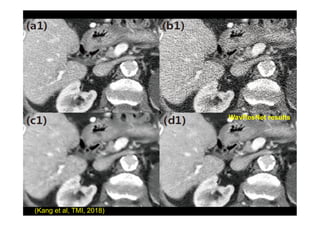

WavResNet results

(Kang et al, TMI, 2018)

MBIR Our latest Result

C D WavResNet results

Full dose Quarter dose